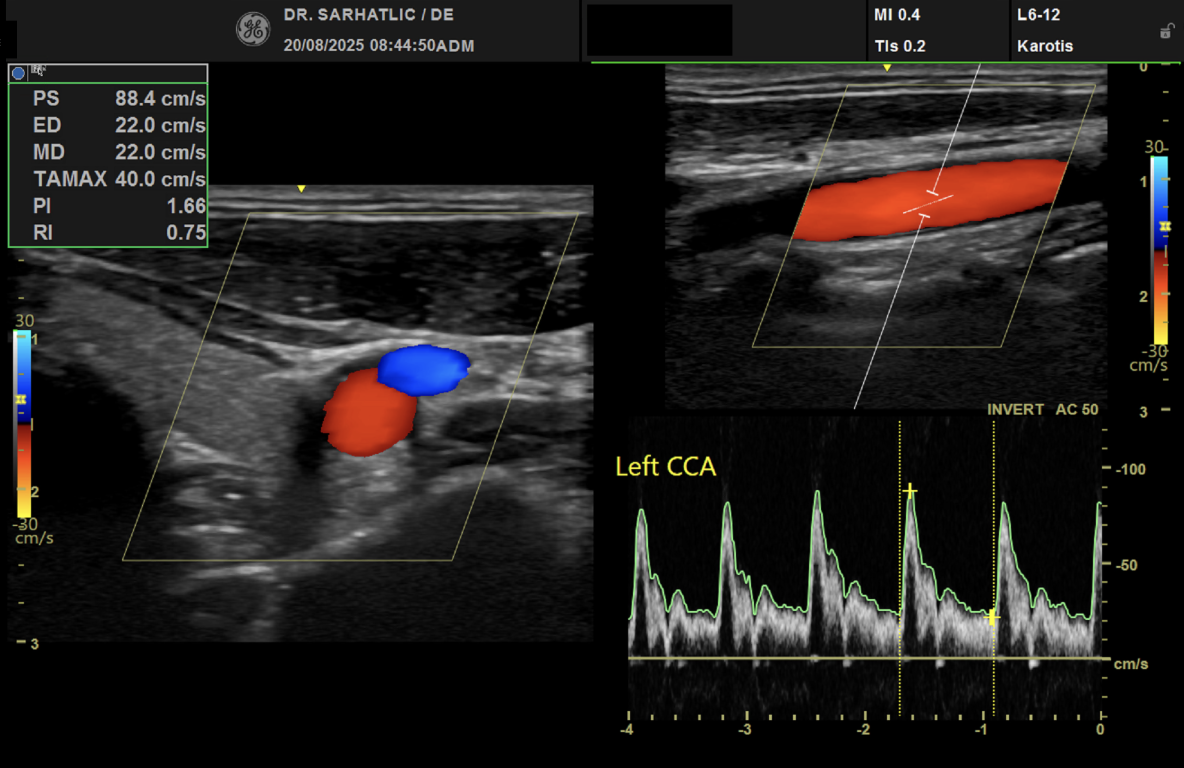

MODERNE ULTRASCHALLDIAGNOSTIK- Modernes Farbdoppler-Ultraschallgerät

- Hochauflösende Schallköpfe

- Detaillierte Organuntersuchungen

- Ultraschall der Gefäße (z. B. Halsschlagadern)